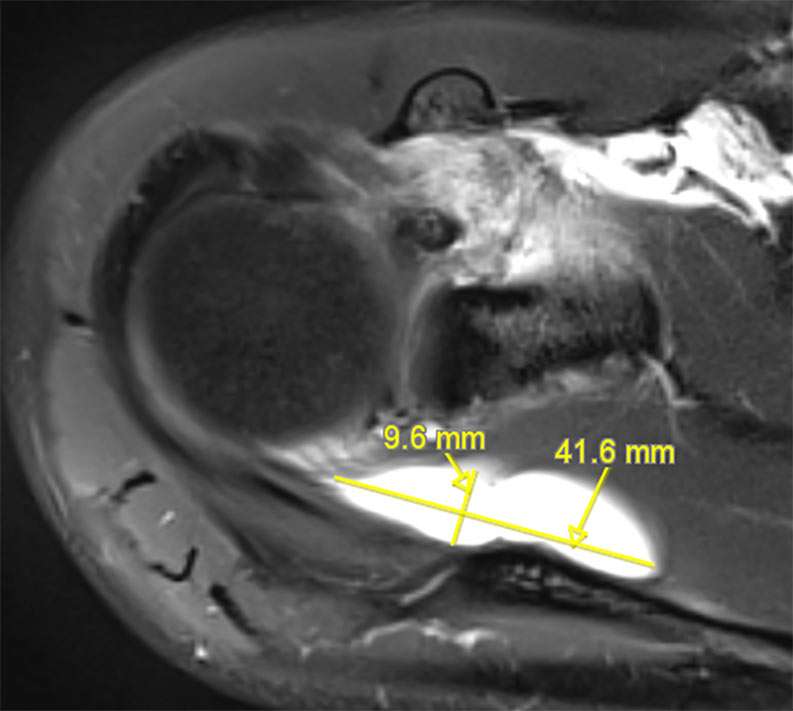

F02: SLAP VIII + MASSIVE COMPRESSIVE CYST ON SSN

Shoulder Right

Patient 39 y/o, Female, Right-hand dominant